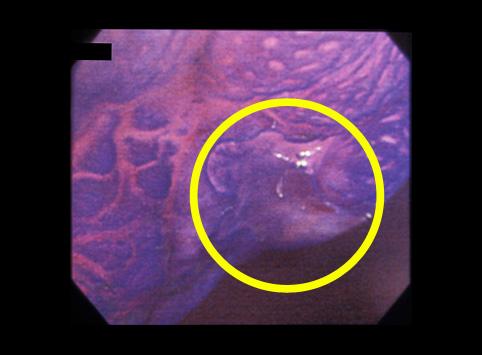

부위(장기별) 대장/직장

검사방법 내시경

종양의 육안분류 0형(표재형)/IIc형(IIc+IIa)

종양의 최대경(밀리미터) 10~14

종양의 심달도 m